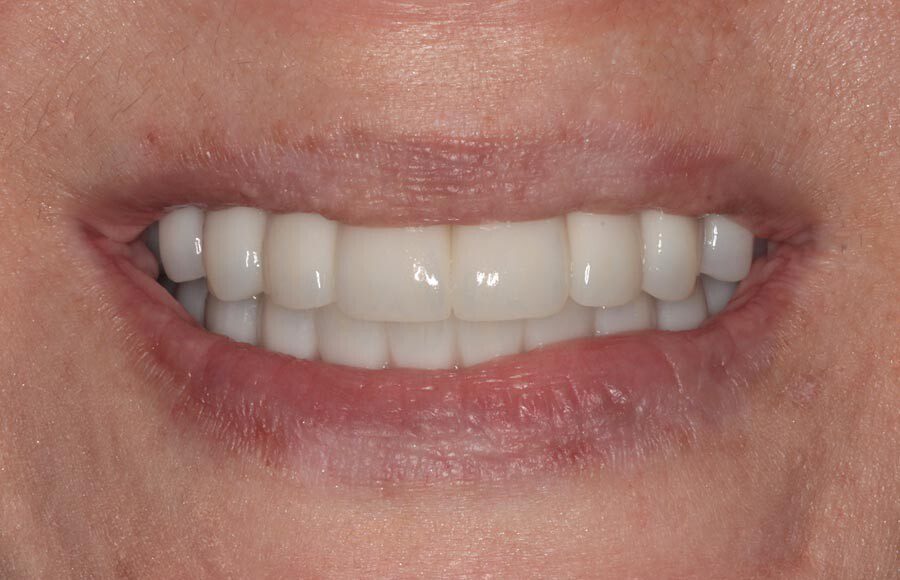

The definitive bridges are delivered, the bite is verified, and the screws are torqued down firmly. The final result is strong, functional, and esthetic restorations that will serve the patient well for years to come.

The patient couldn’t be happier with her new smile. We have improved not only her esthetics but her oral health as well. She now has beautiful restorations she can keep for years to come. Contact us if you would like to have a consultation and see if this is the right treatment for you!